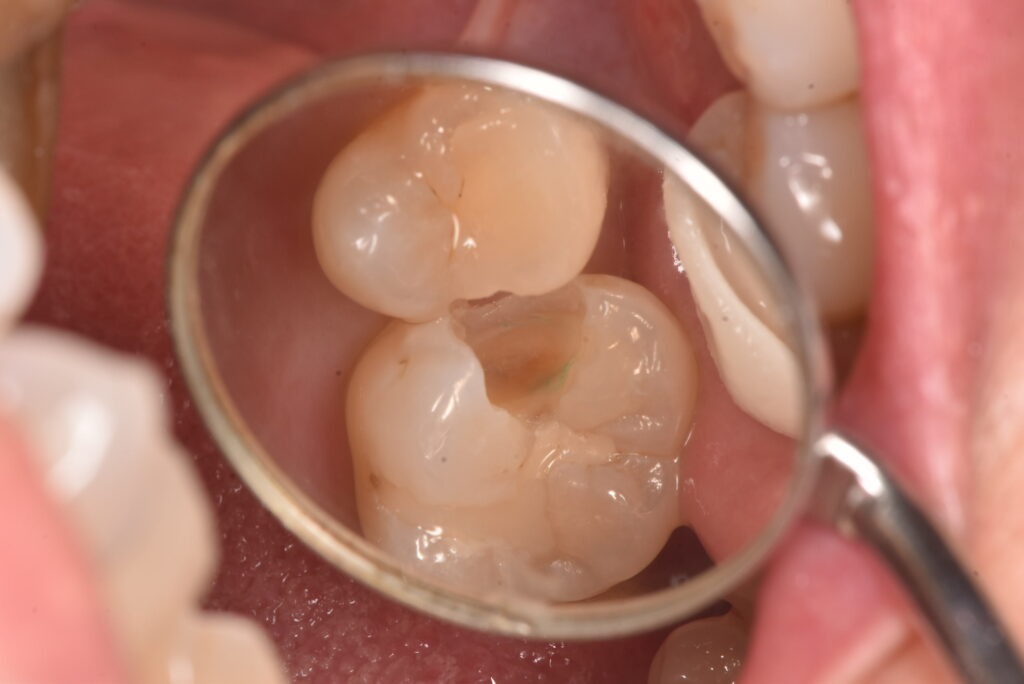

古いつめものの下の部分も含め、かなりの範囲に広がっていました。それよりも問題なのは、一番最後の写真に写っている削った部分の茶色い部分は、ほぼ神経の真横、ということです。そこまでの大きさなのかは、処置前には全く分かりませんでした。

この状態からは、歯の神経もとることになりえる、ということがお分かりかと思います。一番考えていただきたいこととして、最初の処置前写真から、最後の状態になることを想像できたでしょうか?ということです。

「痛みがなかったのに、歯医者でむし歯があると言われて、治療したら神経をとることになった。おかしい!」に対する回答の一つが上のケースになります。処置前は痛み等の症状はありませんでした。